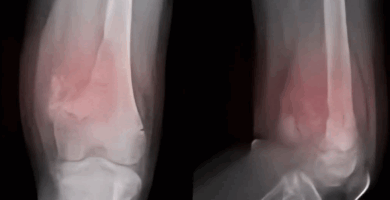

RODILLA HINCHADA, TAMBIÉN CONOCIDA COMO DERRAME EN LA ARTICULACIÓN DE LA RODILLA